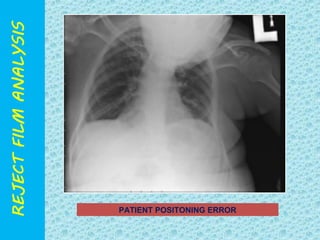

POSITIONING ERROR

PATIENT POSITONING ERROR